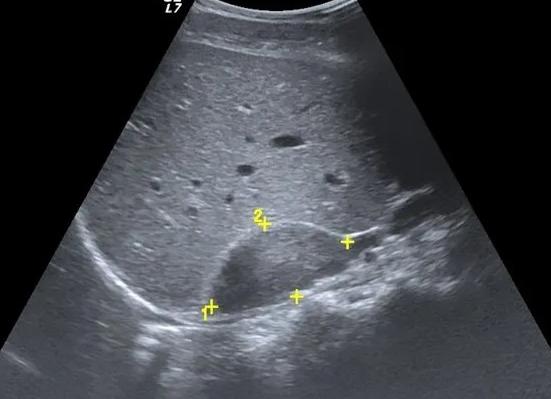

Что показывает УЗИ надпочечников: как делают, показания к исследованию